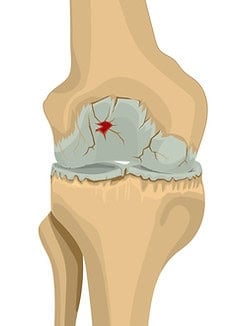

Viertes Stadium

Schwere Arthrose

Dies ist das am weitesten fortgeschrittene Stadium der Arthrose. Der Gelenkspalt ist sehr gering, mehr als 60% des Knorpels sind abgenutzt und der Zustand verschlechtert sich weiter. Die Anzeichen sind unübersehbar und äußern sich in ständigen Entzündungen, Knieschmerzen und Steifheit. Es gibt weniger Gelenkflüssigkeit, die Reibung ist höher und es gibt erhebliche Beschwerden bei der Bewegung.